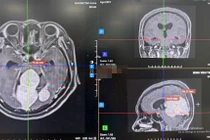

Bác sĩ chuyên khoa thần kinh sẽ khai thác kỹ tiền sử bệnh, tần suất và tính chất cơn đau, đồng thời chỉ định các xét nghiệm hoặc chẩn đoán hình ảnh như MRI, CT scan, điện não đồ (EEG) hoặc siêu âm mạch cảnh để xác định nguyên nhân chính xác.

Gần đây, Bệnh viện Trung ương Quân đội 108 đã tiếp nhận một bệnh nhân nữ, 56 tuổi với khối u màng não rất lớn, vùng liềm, lều tiểu não, chèn ép sâu trong nhu mô não.

Bệnh nhân nhập viện trong tình trạng đau đầu, giảm thị lực. Kích thước khối u lớn (gần 8cm), tăng sinh mạch và vị trí phức tạp, tiềm ẩn nhiều rủi ro như mất máu, ảnh hưởng thị lực.